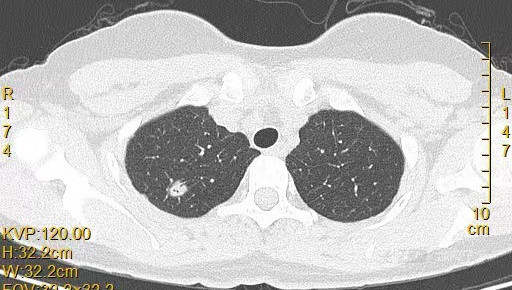

患者女,44岁,无特殊症状,做体检时发现右肺结节。查到1年前的体检CT片,右上肺当时就有一个直径约3mm的微小结节。两次检查检查图片如下:

以下三张为1年前CT片: